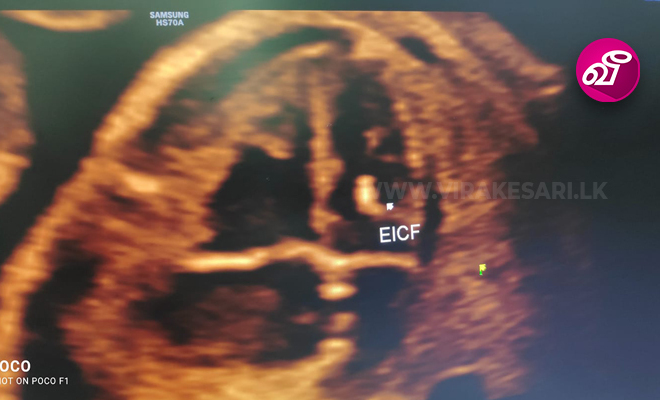

இந்நிலையில் தற்போது இன்ட்ரா கார்டியாக் எக்கோ எனும் நவீன முறையில் இதயத்தில் ஏற்பட்டிருக்கும் பாதிப்பை துல்லியமாக அவதானிக்கிறார்கள்.

இத்தகைய பரிசோதனையின் போது உங்கள் காலின் தொடை பகுதியிலிருந்து மிக நுண்ணிய குழாய் ஒன்றினை உள்ளே செலுத்தி, நேரடியாக இதயப் பகுதியில் உள்ள பாதிப்புகளை கண்டறிகிறார்கள்.

இந்த பரிசோதனையில் இதய பாதிப்பு- இதய தசைகளில் ஏற்பட்டிருக்கும் பாதிப்பு - இதய ரத்த நாளங்களில் ஏற்பட்டிருக்கும் அடைப்பு பாதிப்பு - சீரற்ற இதயத்துடிப்பு- என இதயம் சார்ந்த அனைத்து பாதிப்புகளையும் துல்லியமாக அவதானிக்க இயலும். இது சிகிச்சையை தீர்மானித்து, முழுமையான நிவாரணத்தை வழங்க உதவுகிறது'' என்றனர்.